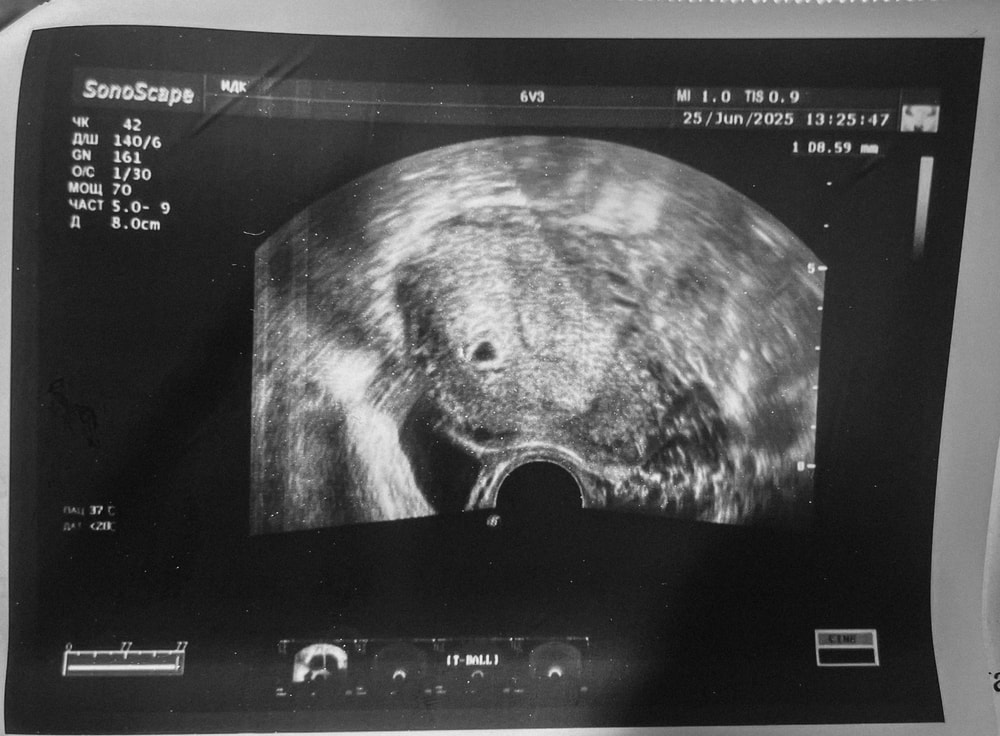

Маточная беременность 5 недель 1 день 🥹

Сходила впервые на узи: увидели плодное яйцо (СВДПЯ - 8,5 мм) и желточный мешочек (2 мм). На следующей неделе пойду смотреть эмбрион и СБ 🙏🏼